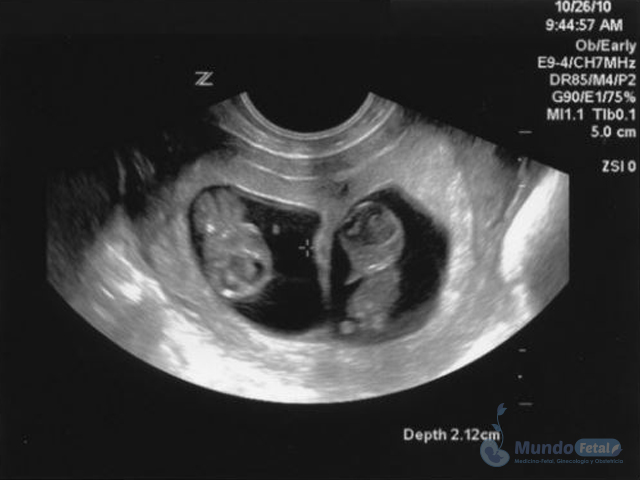

Ultrasonido Embarazo Múltiple

Es esencial detectarlo desde el primer trimestre (especialmente 11-13.6 semanas de gestación) con la intención de conocer el número de bebes, cuántas placentas y bolsas amnióticas, ya que el seguimiento de estos es distinto, esto por los riesgos que conllevan de presentar alguna alteración propia de estos embarazos, indicativos de una vigilancia estrecha y estudios complementarios, durante toda la gestación.